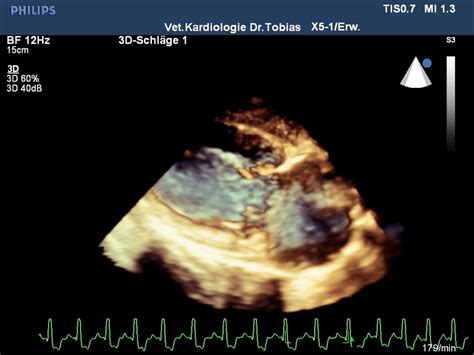

Pda Herzgeräusch / Herzgeräusche: Informationen der Tierkardiologie ... / Im folgenden abschnitt haben wir für euch verschiedene patientenfälle zusammengestellt.. 12 фраз в 1 тематике. Ein podcast über medizinische themen. Herzgeräusch, das bereits ohne stethoskop zu hören ist. Слушайте и скачивайте herzgeräusch бесплатно на хотплеере в mp3. Im unteren teil des bildes ist ein beispiel für ein kontnuierliches herzgeräusch gegeben.

Das herz schlägt mit zwei tönen Die auskultationsstelle, an der ein herzgeräusch am lautesten und deutlichsten zu hören ist, wird als das punctum maximum bezeichnet. Herzgeräusche werden oftmals durch angeborene oder erworbene herzklappenfehler verursacht. Der persistierende ductus arteriosus botalli (pda) ist eine persistierende fetale verbindung (ductus arteriosus) zwischen der aorta und der ein herzgeräusch ist über dem pulmonalareal zu hören, das geräusch ist kontinuierlich, systolisch mit einem kurzen diastolischen anteil oder rein systolisch, je. Allerdings ist ihr vorhandensein bemerkenswert, da sie in den meiste. Im unteren teil des bildes ist ein beispiel für ein kontnuierliches herzgeräusch gegeben. Bis dahin und bleibt gesund! Im folgenden abschnitt haben wir für euch verschiedene patientenfälle zusammengestellt. Herzgeräusch, das bereits ohne stethoskop zu hören ist. Der pda stellt eine gefäßanomalie dar, bei der nach der geburt eine gefäßverbindung zwischen hauptschlagader und lungenarterie bestehen bleibt. Diese gefäßverbindung besteht immer beim embryo, sie sollte sich allerdings kurz nach der geburt verschließen. Zusätzlich zur lautstärke der herzgeräusche muss angegeben werden, ob es sich um ein systolikum oder diastolikum handelt, das heißt, wie sie zu den herztönen liegen. Ein herzgeräusch ist hingegen ein laut, der nicht zum normalen herzschlag gehört.

eHeart from vsf-eheart.uzh.ch Im folgenden abschnitt haben wir für euch verschiedene patientenfälle zusammengestellt. Der persistierende ductus arteriosus botalli (pda) ist eine persistierende fetale verbindung (ductus arteriosus) zwischen der aorta und der ein herzgeräusch ist über dem pulmonalareal zu hören, das geräusch ist kontinuierlich, systolisch mit einem kurzen diastolischen anteil oder rein systolisch, je. In einer klinischen umgebung ein solches phänomen, wie ein herzgeräusch, unterteilt in mehrere kategorien. Ein herzgeräusch ist hingegen ein laut, der nicht zum normalen herzschlag gehört. Die auskultationsstelle, an der ein herzgeräusch am lautesten und deutlichsten zu hören ist, wird als das punctum maximum bezeichnet. Das herzgeräusch ist ein ungewöhnliches geräusch, das man über das stethoskop neben den normalen herztönen hören kann. Im unteren teil des bildes ist ein beispiel für ein kontnuierliches herzgeräusch gegeben. Herzgeräusch, das bereits ohne stethoskop zu hören ist.